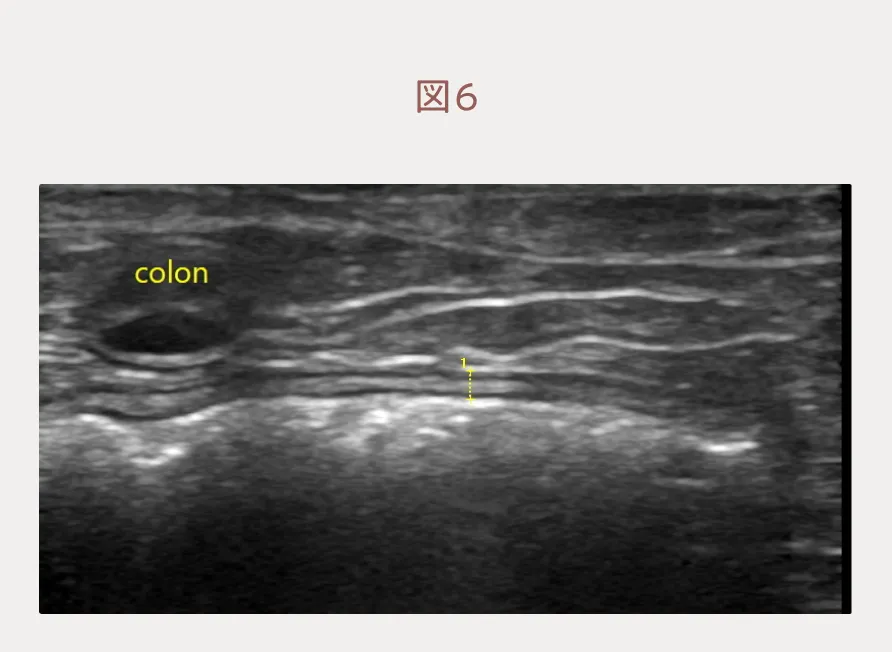

抗がん剤を投与したところ、1週間で劇的な改善が見られました。消化器症状は全て消失し、血便はなく正常便の固さに戻りました。元気も食欲もあり、自宅での生活の質は一変したようです。エコー検査では大腸壁の肥厚・層構造の消失・結腸リンパ節腫大は改善し(図6)、完全寛解と評価しました。今後もなるべく寛解期間が長く、生活の質が維持されることを目指して抗がん剤治療を継続していきます。